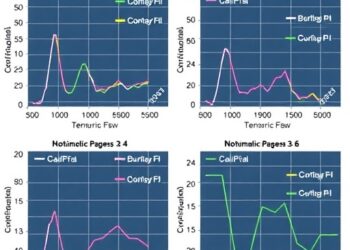

Tobramycin Pharmacokinetics in Cardiac ICU Infants

In the specialized realm of pediatric cardiac intensive care, the precise administration of antibiotics is paramount to safeguarding the vulnerable...